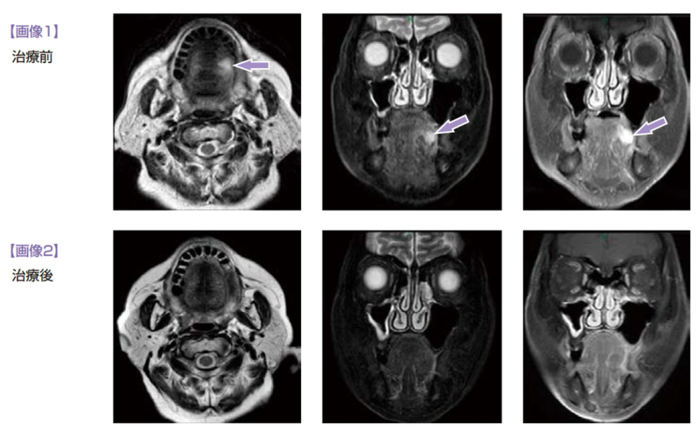

2011年2月、前医で舌左縁のびらんに対し精査を行い、生検で扁平上皮癌と診断された。MRI で深部浸潤が疑われ(画像1)、舌半切+筋皮弁再建の説明を受けられたが、趣味の歌謡を続けたいという希望があり手術を拒否された。放射線治療も機能障害の可能性があり拒否された。化学療法も同意が得られなかった。免疫療法を希望され前医でペプチドワクチンを予定したが、HLA タイピングが不適合で受けられなかった。4 月に当院を受診となった。受診時の病期分類はcT2, cN0, cM0, cStⅡであった。

4 月下旬からアルファ・ベータT 細胞療法療法を施行した。初回治療直後に2 時間ほどの倦怠感(グレード2) と37.0℃の発熱を認めた。2 回目の治療後には1 時間ほど関節痛(グレード1)、生あくび、体が火照る感じが継続し、収縮期血圧が200 以上と上昇した(グレード2)。いずれの症状も、末梢輸液をしながら経過観察したところ自然に消失した。このとき3 回目以降の治療を中止することも検討したが、本人の強い希望があり治療を継続することとした。3 回目治療前に降圧薬を増量し、それ以降は有害事象を認めなかった。8月上旬、1 コース(6 回) の治療が終了した時点でMRI を行い、画像上CRとなった(画像2)。しかし肉眼的には僅かな凹凸を認め、PR と判断した。11月上旬、2コースの治療が終了した時点で、本人の希望にしたがい治療を終了した。その後、2012年2月上旬のMRI 検査でも寛解を維持している。